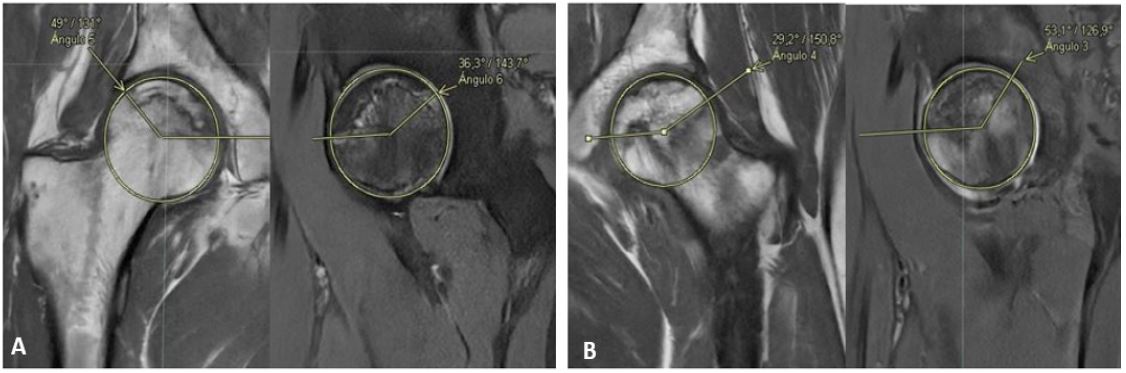

We report a case of a 31 years-old male, with medical history of obesity (BMI 31) and severe pneumonia by CoViD-19 previous, during hospital stay requires intravenous steroids (total dose 60 mg of dexamethasone) and immobilization secondary prostration at least one month. He consults one year later for pain in left groin and secondary limp. Physical examination showed abduction, external rotation and flexion diminished in left hip. Initial X-ray evidence areas of low density both femoral heads (Figure 1). Following study with simple Magnetic Resonance Image (MRI) (Figure 2) showed right hip with changes of necrotic bone without edema, a calculated Kerboul angle of 274o, in left hip edema and areas on necrotic bone, with an anterocentral subchrondral bone fracture of femoral head, Kerboul angle of 257º.

Figure 1: Bilateral hip X-ray Anterior-posterior view showing low density zones (arrows) in both femoral heads. Following study with simple magnetic resonance imagen (MRI) (Figure 2) showed right hip with changes of necrotic bone without edema, a calculated Kerboul angle of 274o, in left hip edema and areas on necrotic bone, with an anterocentral subchrondral bone fracture of femoral head, Kerboul angle of 257o.